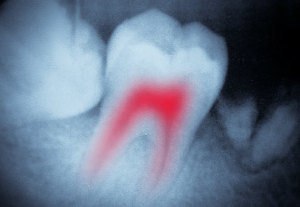

You will need a root canal if your tooth has damage to its dental pulp, the soft tissue that surrounds nerves in the center of the tooth.